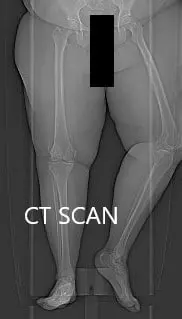

Topographic CT images of the weight-bearing Right and Left knee respectively.

A few weeks prior, a CT scan of the bilateral lower extremities was performed to obtain detailed data on the patient’s unique anatomy and biomechanics of the knees. A preoperative plan was formed to guide the surgeon in bone cuts and offsets. Disposable instruments were custom made for the patient. Unique customized implants were made to match the patients cut surface of the knee.